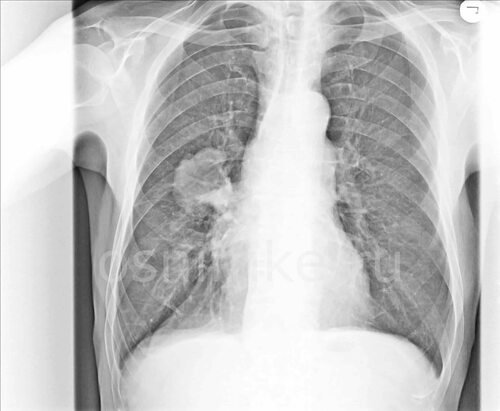

Раковые опухоли на рентгене

Опухоль легкого на рентгене

Опухоль в легких на рентгене

Новообразование в легких на рентгене

- Рентгенография легких